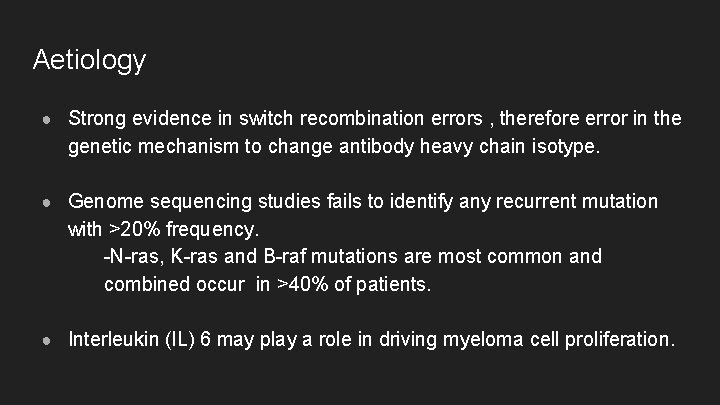

Aetiology ● Strong evidence in switch recombination errors , therefore error in the genetic mechanism to change antibody heavy chain isotype. ● Genome sequencing studies fails to identify any recurrent mutation with >20% frequency. -N-ras, K-ras and B-raf mutations are most common and combined occur in >40% of patients. ● Interleukin (l. L) 6 may play a role in driving myeloma cell proliferation.